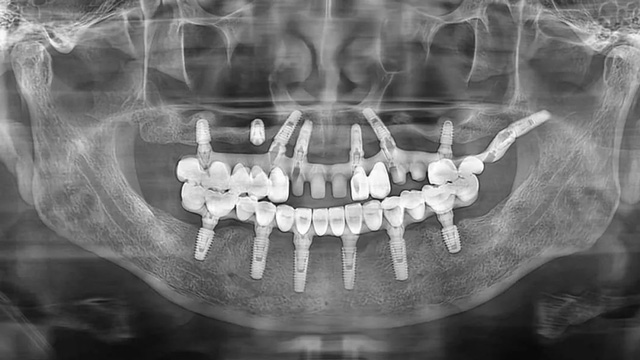

王先生的口腔全景片(2021年9月/新橋口腔成都玉雙院區(qū))

當(dāng)天的面診和檢查結(jié)果顯示,王先生在金牛區(qū)某口腔診所種植的6顆種植體中,有一顆出現(xiàn)松動(dòng),一顆種植體頸部暴露。

王先生全口種植后全景片(2024年4月/新橋口腔成都衣冠廟院區(qū))